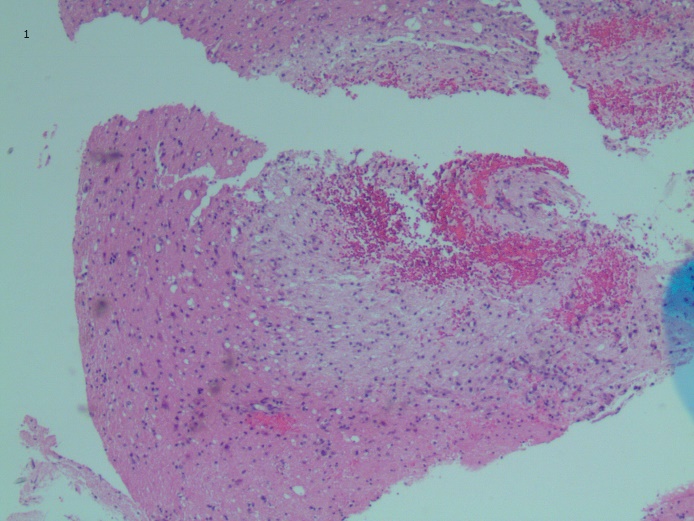

Brian biopsy results of the left occipital lesion showed cortex and white matter involvement with few scattered macrophage infiltrates, gliosis, hemorrhage, and rare hemophagocytic cells (Figure 3).

Figure 3. Brian biopsy of the left occipital lesion showed cortex and white matter involvement with few scattered macrophage infiltrates, gliosis, hemorrhage, and rare hemophagocytic cells (arrows). Hematoxylin-eosin, original magnification ×4 (top) and ×20 (bottom).